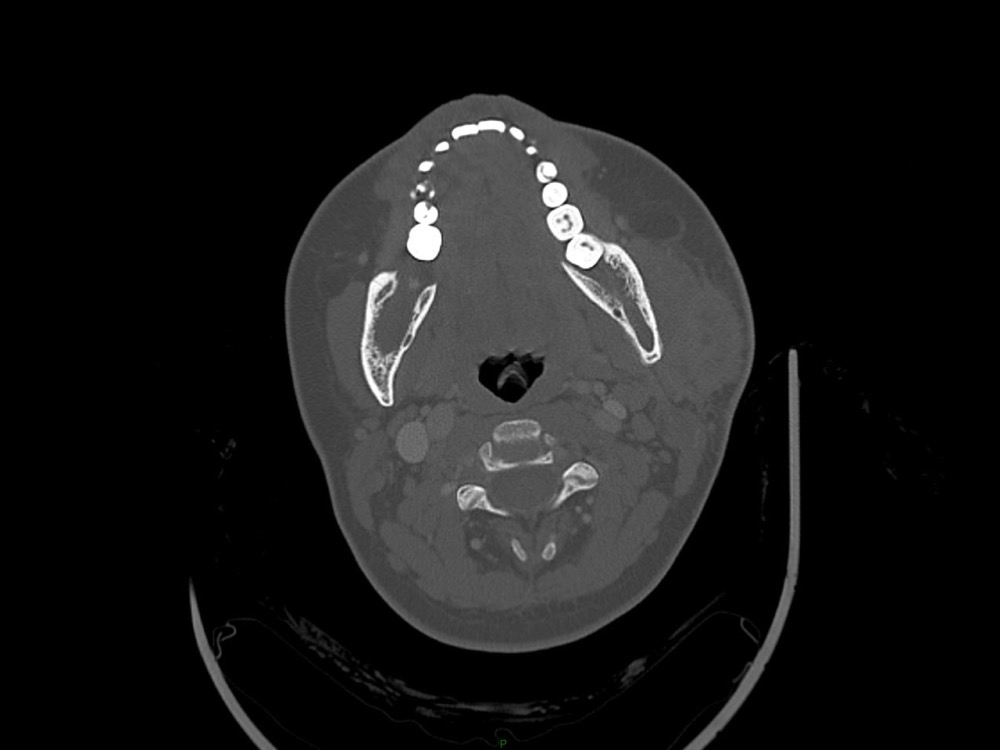

Arsovic / Perrot / Miquel 18/05/2022